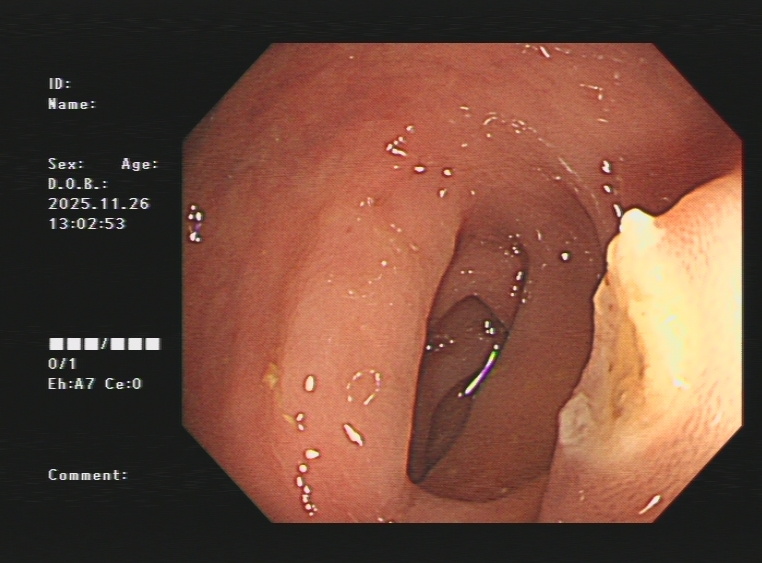

3.下消化道出血常见病因包括痔疮、肛裂、肠息肉、结肠癌、肠道憩室、炎症性病变(溃疡性结肠炎、缺血性肠炎、 感染性肠炎等)。以下是一些常见的下消化道出血内镜图片:

结肠憩室出血